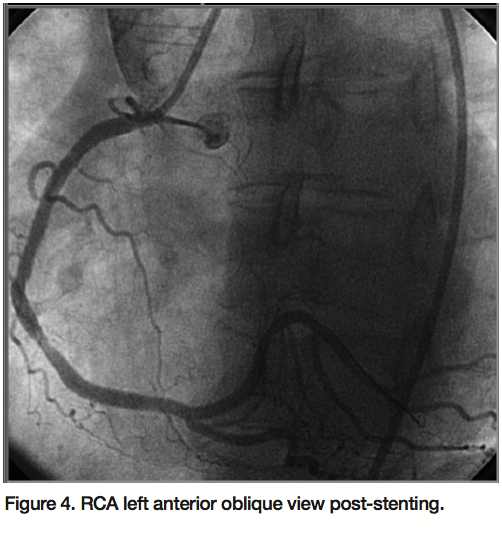

exchange for a 6 Fr sheath. Close fluoroscopic inspection of the femoral artery area revealed part of a sheath (Figure 1). In order to retrieve the micropuncture sheath from the StarClose™ clip, the left femoral artery was cannulated and a snare was passed from this access site into the proximal right femoral artery. The micropuncture sheath was snared off the StarClose™ device and was safely retrieved through the left femoral artery (Figure 2). An aortogram and runoff images showed good distal leg blood flow without evidence of distal embolization or ischemia. Following this, RCA was successfully stented through the left femoral artery access site (Figures 3 and 4).